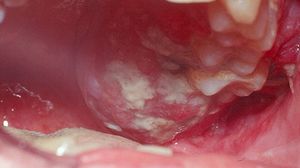

الوكيل الإخباري- حذر أطباء في بريطانيا من أن القرح الفموية التي لا تختفي قد تكون مؤشرًا على سرطان الفم، خاصة سرطان الخلايا الحرشفية، وهو النوع الأكثر شيوعًا. ويبدأ غالبًا كقرحة بسيطة أو بقعة حمراء/بيضاء داخل الفم.

الأعراض تشمل: تورم في الفم، صعوبة في البلع، تغيّر في الصوت، وألم أثناء الأكل أو التثاؤب.

📌 الاكتشاف المبكر يزيد فرص الشفاء إلى 99%، بينما تنخفض إلى 50% في المراحل المتقدمة، التي قد تتطلب جراحة ترقيع الجلد لإزالة الأجزاء المصابة وزرع أنسجة جديدة.